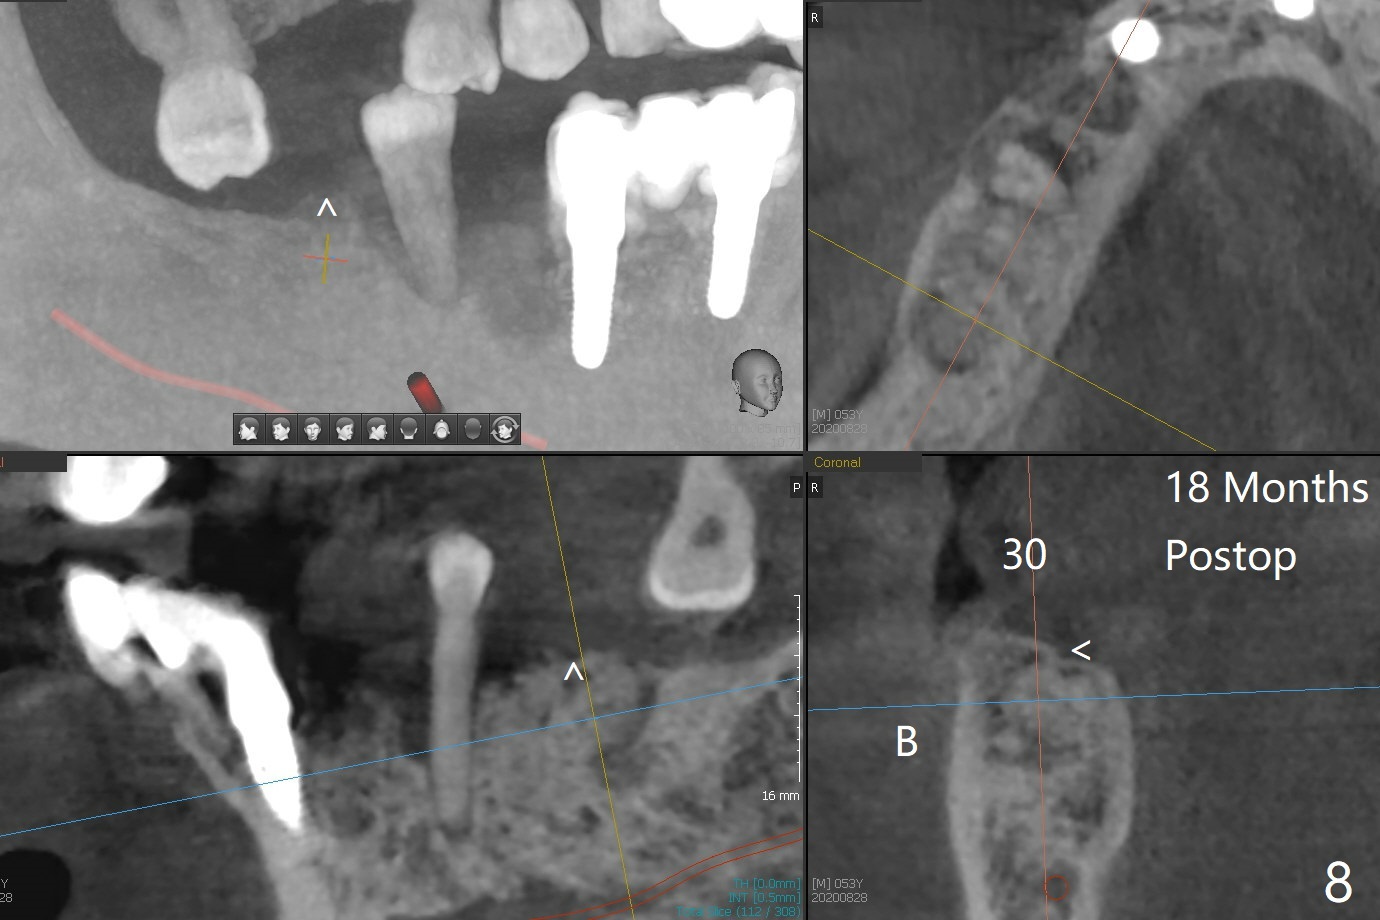

A 52-year-old man with poor dentition has concept of socket preservation when he wants extraction at #30. There is bone loss with the presence of the septum (Fig.1,2 *). Mixture of Vanilla graft and Osteogen is packed around the septum (Fig.3). With blood supply from the septum, the allograft should be more efficiently converted to the native bone than without the septum. The socket is closed with Osteogen plug and suture (Fig.4). In fact the bone height increases by 2.4 mm over the septum 11 months postop (Fig.5,6). In contrast there is apparently no bone regeneration in the socket of #28 four months postop without bone graft (Fig.7). Implant to be placed in the "empty" socket may fail. With bone graft, the ridge at #30 is higher than the surrounding bone 18 months postop (Fig.8 ^) with formation of the cortex on the top of the alveolus <). The average bone density is 1500 units. In contrast, without bone graft, the buccal plate at #28 is missing 11 months postop (Fig.9 >) with average bone density at 500 units. The implant at #28 should be long to engage to the apical native bone (Fig.10) with incision in case of need for bone graft. Sticky bone will be placed mesial to #29.